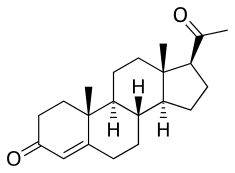

Progesterone (Prometrium, Utrogestan), the natural progestogen in the body and one of the most widely used progestogen medications. | |

Chemistry

All currently available progestogens are steroidal in terms of chemical structure.[1] Progestogens include the naturally occurring progesterone and the synthetic progestogens (otherwise known as progestins).[1] Progestins can be broadly grouped into two structural classes—chemical derivatives of progesterone and chemical derivatives of testosterone.[1] Progesterone derivatives can be classified into subgroups including pregnanes, retropregnanes, norpregnanes, and spirolactones.[1] Examples of progestins of each of these subgroups include medroxyprogesterone acetate, dydrogesterone, nomegestrol acetate, and drospirenone, respectively.[1] Testosterone derivatives can be classified into subgroups including androstanes, estranes (19-norandrostanes), and gonanes (18-methylestranes).[1][281] Examples of progestins of each of these subgroups include ethisterone, norethisterone, and levonorgestrel, respectively.[1] Many progestins have ester and/or ether substitutions (see progestogen ester) which result in greater lipophilicity and in some cases cause the progestins in question to act as prodrugs in the body.[1]